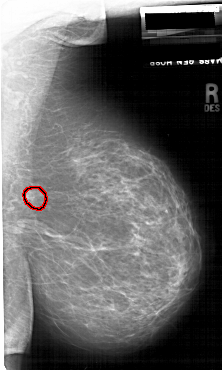

A_1745_1.LEFT_MLO

LEFT_MLO LINES 6526 PIXELS_PER_LINE 4051 BITS_PER_PIXEL 12 RESOLUTION 43.5 NON_OVERLAY

FILE: A_1745_1.RIGHT_MLO.OVERLAY

TOTAL_ABNORMALITIES 1

ABNORMALITY 1

LESION_TYPE MASS SHAPE IRREGULAR MARGINS ILL_DEFINED

ASSESSMENT 4

SUBTLETY 2

PATHOLOGY BENIGN

TOTAL_OUTLINES 1

BOUNDARY